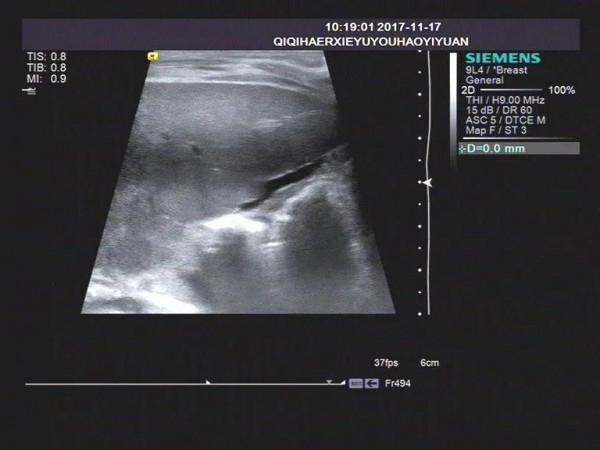

一,超聲顯示無膽囊型:肝門部形成的高回聲,形態各異,可見索狀高回聲,無膽管擴張。

三,均伴有不同程度肝臟、脾臟腫大。早期肝臟普遍回聲增粗增強,中晚期肝臟纖維化、肝硬化樣聲像圖表現。

(筆者見過兩例10月左右幼兒,膽汁性肝硬化晚期,腹水,巨脾,腹壁靜脈怒張,右心增大,心包積液)。